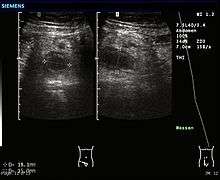

In children the clinical examination is important to determine which children with abdominal pain should receive immediate surgical consultation and which should receive diagnostic imaging.[40] Because of the health risks of exposing children to radiation, ultrasound is the preferred first choice with CT scan being a legitimate follow-up if the ultrasound is inconclusive.[41][42][43] CT scan is more accurate than ultrasound for the diagnosis of appendicitis in adults and adolescents. CT scan has a sensitivity of 94%, specificity of 95%. Ultrasonography had an overall sensitivity of 86%, a specificity of 81%.[44]

Ultrasound

Ultrasonography and Doppler sonography are useful to detect appendicitis, especially in children. Ultrasound can show free fluid collection in the right iliac fossa, along with a visible appendix with increased blood flow when using color Doppler, and noncompressibility of the appendix, as it is essentially a walled off abscess. Other secondary sonographic signs of acute appendicitis include the presence of echogenic mesenteric fat surrounding the appendix and the acoustic shadowing of an appendicolith.[45] In some cases (approximately 5%),[46] ultrasonography of the iliac fossa does not reveal any abnormalities despite the presence of appendicitis. This false negative finding is especially true of early appendicitis before the appendix has become significantly distended. In addition, false negative findings are more common in adults where larger amounts of fat and bowel gas make visualizing the appendix technically difficult. Despite these limitations, sonographic imaging in experienced hands can often distinguish between appendicitis and other diseases with similar symptoms. Some of these conditions include inflammation of lymph nodes near the appendix or pain originating from other pelvic organs such as the ovaries or Fallopian tubes.